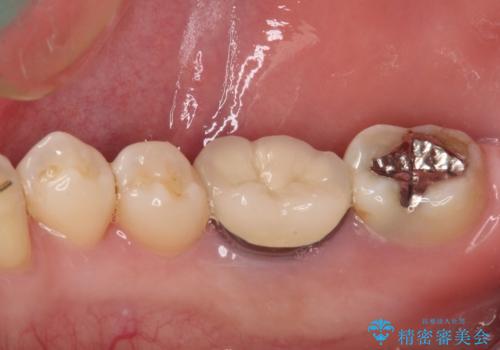

精度の高いセラミックインレーによる修復治療を行うこととしました。

セラミックインレー装着後はフロスの引っかかるストレスから解放され、患者様には大変満足していただきました。